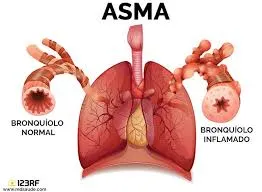

A asma é quando as vias que levam o ar para os pulmões ficam irritadas e inchadas, além de produzirem muco extra, o que dificulta a respiração e causa falta de ar, sendo estes os principais sintomas.

O diagnóstico da asma é clínico, baseado em sintomas como tosse, chiado no peito, falta de ar e aperto no peito, além do histórico familiar de alergias.